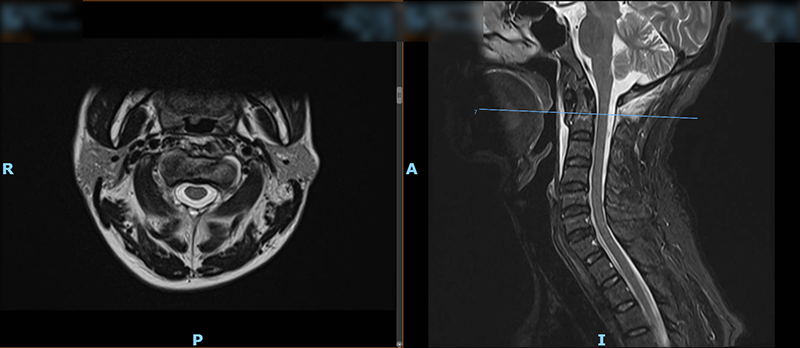

日前,47岁的王先生(化名)因外伤致颈部疼痛、活动受限,在家人的陪同下,他来到柳州市人民医院脊柱外科就诊。结合MRI检查结果,医生诊断王先生为枢椎齿状突II型骨折,需手术治疗,王先生被收入脊柱外科病房。

▲术前MRI检查结果

脊柱外科主任胡朝晖博士介绍,在颈椎损伤中,齿状突骨折是累及寰枢椎区域稳定性的严重损伤,发生率约占颈椎损伤的10%,由于具有特殊的解剖学结构,其不愈合发生率较高,不稳定因素的存在,可导致急性及延迟性颈髓压迫并危及生命。齿状突骨折分为三型,其中Ⅱ型骨折是指涉及齿状突颈部的骨折,此型骨折最为常见并且不稳定,可见向前或向后移位。并且,寰枢椎部位解剖结构复杂,手术区域静脉窦血运丰富,出血凶险,置钉时在狭窄区域需避开外侧椎动脉,内侧脊髓,真是“失之毫米,即是灾难”,一旦操作失误或并发症,病人就可能高位截瘫,丧失呼吸功能生命难以维持。